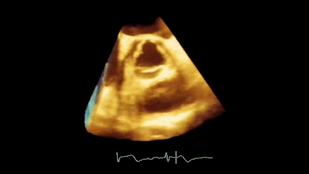

Новое издание широко известного практического руководства по клинической эхокардиографии подготовлено экспертами в области интерпретации эхокардиографических изображений и данных допплерографии. В каждой главе описана определенная патология, приведены ее эхокардиографические изображения с правильной интерпретацией, графики и рисунки, раскрывающие патофизиологию, а также рекомендации по лечению. Представлены новые методы диагностики и лечения структурных патологий сердца, включая транскатетерные методы. В конце каждой главы приведена таблица сводных данных по получению и интерпретации эхокардиограмм.

Подчеркивается особая роль эхокардиографии в принятии клинических решений и прогнозировании клинических исходов. Издание дополняют видеоизображения в режиме реального времени.